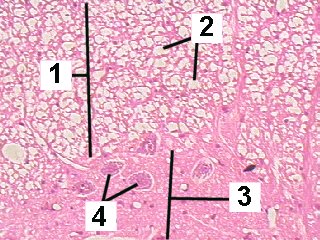

A higher magnification of the white and gray matter of the spinal cord.

Fig 026-006 |